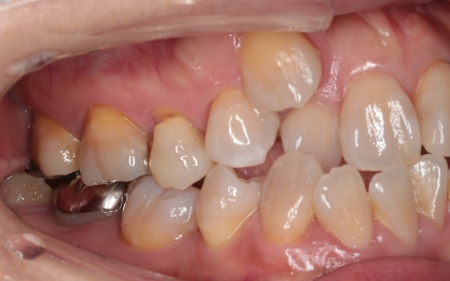

50代女性 インプラントアンカーを併用したワイヤー矯正で乱れた歯並びと噛み合わせを改善した症例

診断結果 拝見したところ、上下の歯がデコボコに乱れて生えていました。

歯の大きさに対して顎が小さいため、歯が正常に並びきらず、全体的な噛み合わせのバランスも崩れています。

噛み合わせを詳しく検査したところ、実際にしっかりと噛み合っているのは一部の歯だけで、このまま放置すると特定の歯に負担が集中し、将来的に痛みや違和感が生じるおそれがあります。

また、銀歯が装着されている右下奥歯は以前神経を抜く治療がされていましたが、現在は歯の具合が良好とはいえず、温存が難しい状態です。